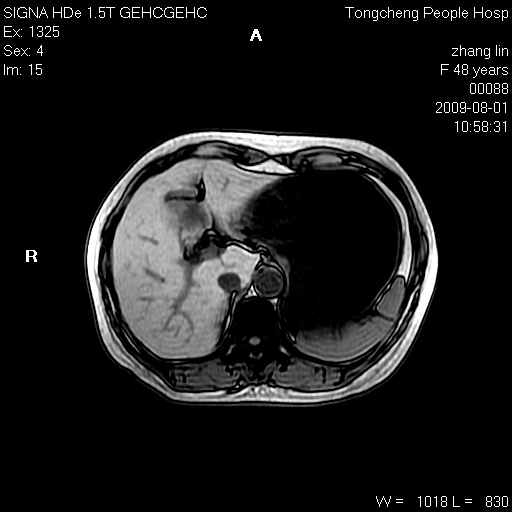

女,48岁。健康体检,彩超发现右肾占位性病变。平素健康。

临床诊断:右肾占位性病变,性质待定(囊肿?肿瘤?)。

上中腹部mr平扫+增强扫描,图像如下:

右肾上极见一类圆形病灶,t1wi呈等信号t2wi呈等高混杂信号,三期增强无强化,边界清---考虑囊肿出血。

同反相位均表现为等信号,病变无强化,考虑含蛋白的囊肿可能,弥散加权相或许有些帮助,